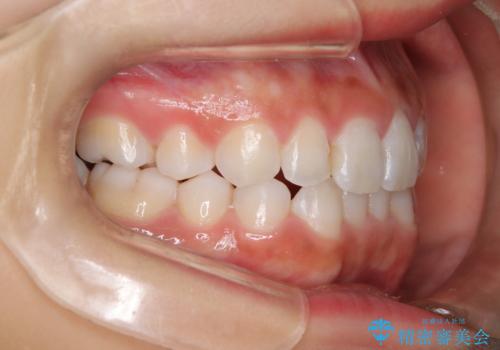

- 子供のころに矯正治療をされていたが、後戻りをしてしまったという20代女性の患者様です。上顎左右の2番が、咬合時に下顎の歯よりも内側に入っているクロスバイトという状態でした。奥歯の咬合関係は変えずに、マウスピース矯正にて前歯の並びを綺麗なアーチに仕上げました。再度後戻りしてしまうリスクを軽減させるために、リテーナー(保定装置)をお渡ししています。